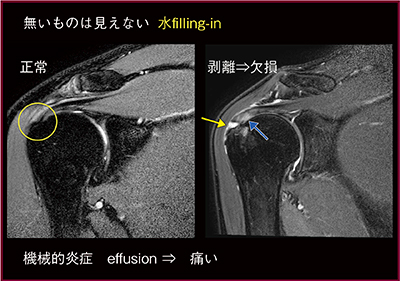

●無いものは見えない

腱板断裂や関節唇損傷は欠損である。欠損部は滑膜も損傷するため,滑膜炎やびらんが生じて浸出液が漏出し,欠損部にfilling-inする。水がfilling-inした部分が,(脂肪抑制)T2強調画像で高信号となることで病変を読影できるが,逆に言えば,浸出液がfilling-inしていない場合は見落としてしまうため注意が必要である(図5)。

図5 腱板剥離:欠損部への水filling-inによる高信号